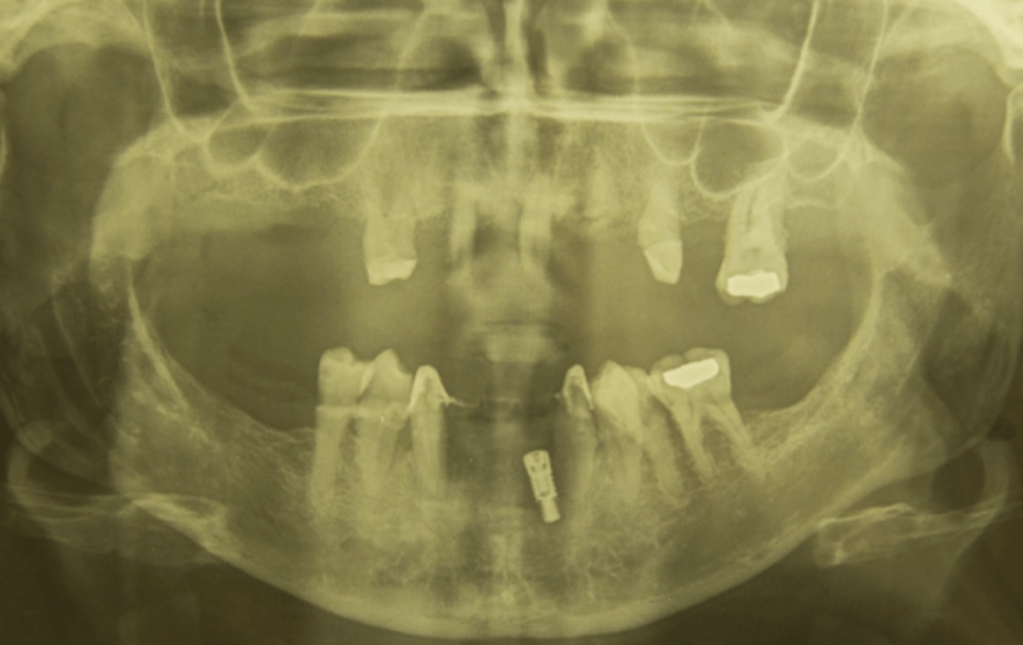

Below is the X-ray I had done last week.